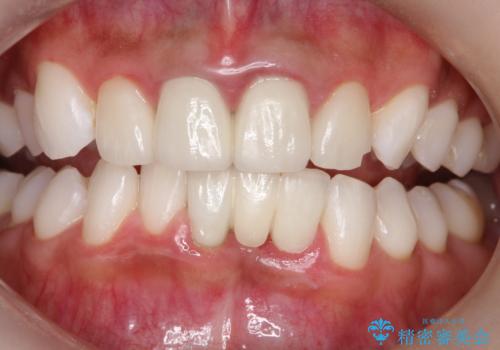

[エアフロー] スプレーの噴射によりしつこい色素沈着やプラークを除去

![[エアフロー] スプレーの噴射によりしつこい色素沈着やプラークを除去の症例 治療後](https://seimitsushinbi.jp/wp/wp-content/uploads/2021/11/IMG_0004-500x350.jpg?v=1636593307)